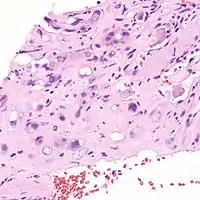

| Micrograph of an epithelioid hemangioendothelioma of the liver. | |